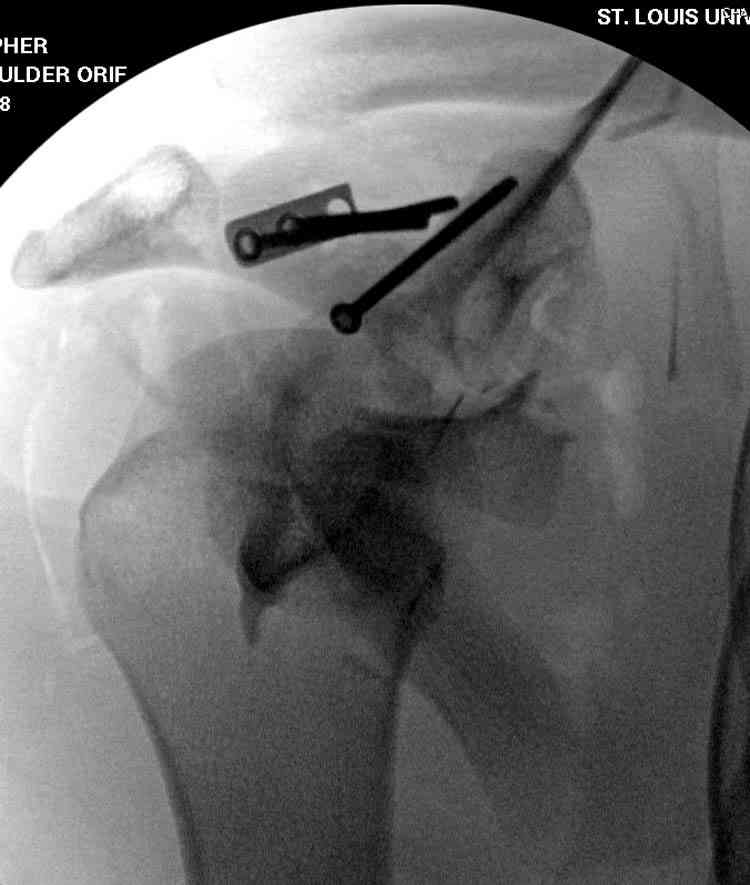

На снимке (№6 компьютерная томограмма и 3D №7) перелом клювовидного отростка.

Передним дельтопекторальным Bankart доступом намного легче провести фиксация отростка, но тогда репозиция и фиксация колонн затрудняется, поэтому был применен стандартный Judet задний доступ.

Репозицию смогли сделать пальцами через щель между

шейкой и телом лопатки (последний 3D снимок)

Двумя шурупами сзади на пластине (вместе шайбы)

провели удержание репозиции, а фиксацию провели

следующим косым шурупом.

Последующие этапы на снимках.